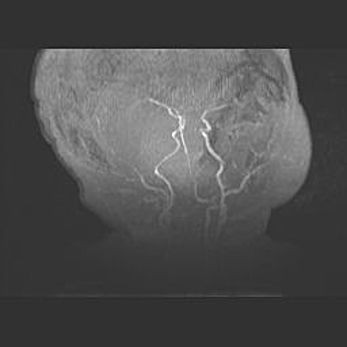

Подострая гематома правой гемисферы мозжечка.

Наружная гидроцефалия.

Возраст: 15 дней

Вес: 3100 г

Пол: женский

Окружность головы: 37 см

Срок гестации: 35-36 недель

При открытой наружной форме гидроцефалии у новорожденных расширяются и переполняются субарахноидные пространства.

Кровоизлияния в мозжечок имеют две клинико-анатомические формы: полушарные гематомы и кровоизлияния в червь.

К появлению этой патологии может привести: повреждения головного мозга, возникающие в результате асфиксии и гипоксии плода при беременности, или травмы во время родов. Редко гематома мозжечка может быть результатом первичной коагулопатии и сосудистой мальформации, диссеминированном внутрисосудистом свертывании, изоиммунной тромбоцитопении.